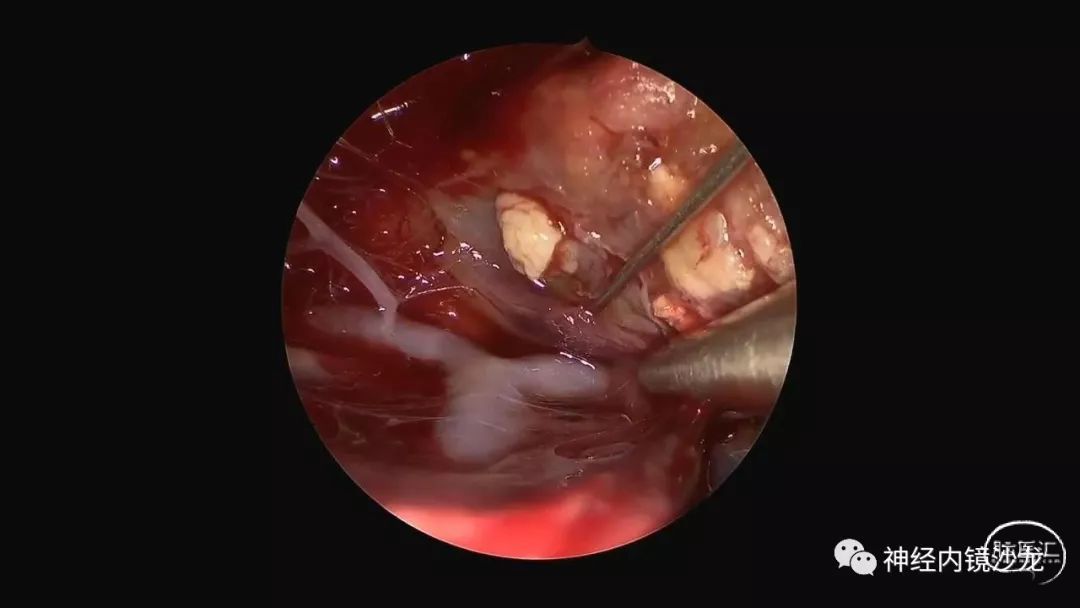

精彩图表

从事神经外科十余年,擅长神经外科肿瘤诊治,尤其是神经内镜微创手术治疗垂体瘤、颅咽管瘤、脑膜瘤等颅底肿瘤